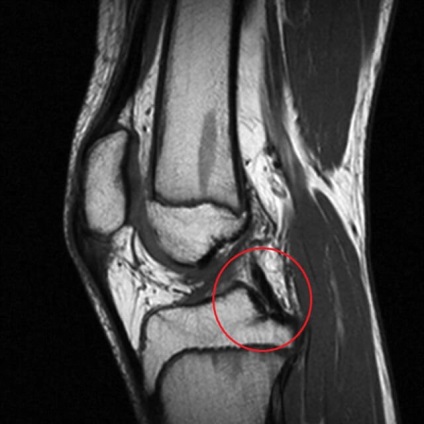

osteochondritis dissecans

Aszeptikus nekrózisa femorális condylus miatt törés a porc, és egy vékony réteg a csont alatta. Ennek oka a fokozott fizikai aktivitás, mert - térdfájdalom serdülők és gyermekek a háttérben osteochondritis fordul elő magas sporttevékenység.

Gyakran a betegség nem differenciált a rándulás, hogy később képes előidézni blokád a térd és a további pusztítás az ízületi felület.

csontvelő ödéma a térdízület